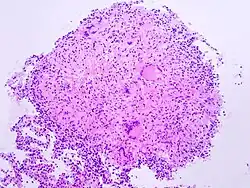

Die Langhans-Zelle oder Langhans-Riesenzelle ist eine aus dem retikuloendothelialen System (RES) entwickelte oder von einer Epitheloidzelle abgeleitete Zelle, die der körpereigenen Infektabwehr zuzurechnen ist.

Die Funktion der Riesenzellen (welche nicht mit den phagozytierenden Langerhans-Zellen verwechselt werden sollten) vom Langhans-Typ ist weitgehend unbekannt. Sie sind bei granulomatösen Erkrankungen verschiedener Ursache nachweisbar, etwa bei Infektionskrankheiten wie Tuberkulose, Lepra oder Schistosomiasis und chronischen Entzündungen wie Morbus Crohn, rheumatoider Arthritis und Sarkoidose.

Sie hat einen Durchmesser von bis zu 0,3 mm, ist nur in geringem Maße phagozytisch aktiv und auf die Sekretion lysosomaler Enzyme spezialisiert. Charakteristisch ist die hufeisenförmige Anordnung der zahlreichen Zellkerne.